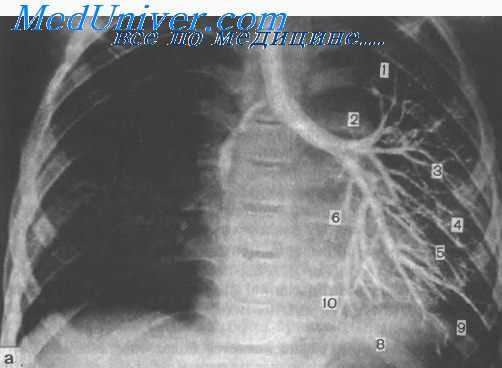

Клиническое течение порока различно и зависит от осложняющих его процессов, чаще всего инфицирования. Более типичны рентгенологические данные. В заднемедиальных отделах верхней доли выявляется округлое иегомогеиное затемнение, на фоне которого можно видеть одну или несколько кистозиых полостей. При бронхографии контрастное вещество обычно не проникает в этот участок. Достоверный дооперационный диагноз секвестрации может быть установлен при аортографии, когда выделяется тень аберрантного сосуда, отходящего от аорты.

Рентгенологическая картина достаточно типична. На прямой рентгенограмме определяется повышенная прозрачность пораженной части легкого. Органы средостения смещены в здоровую сторону в большей пли меньшей степени, в зависимости от вздутия паренхимы. Легочный рисунок н области эмфиземы обеднен или отсутствует, в коллабированных отделах, наоборот, усилен. Бронхологическое исследование и контрастирование сосудов легких позволяют установить точный диагноз н определить степень нарушения функции пораженного легкого.